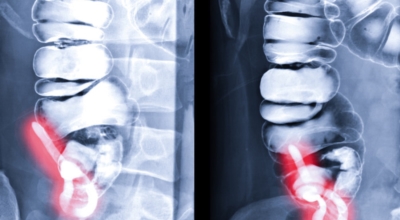

대개 치료의 경우 수술을 진행하는 것이 가장 대표적이며 충수 돌기의 절제를 진행합니다. 항생제를 투여하고 이후 수술을 진행하는데 수술 후에는 금식이 필요합니다. 예외적으로 염증이 심각하여 고름이 발생하면 해당 고름을 우선 제거하고 이후 항생제를 통해 염증을 가라앉힌 후 수술을 진행합니다.

맹장염 초기 증상을 인지하고 병원을 방문하여 맹장염이라고 진단을 받게 되면 복강경 수술로 30분 이내 비교적 안전하게 수술을 마치게 되어요. 하지만 급성 충수염으로 맹장이 터져서 복막염이 생기게 되면 수술도 까다롭고 시간도 훨씬 길어지게 돼요. 급성 충수염의 경우 드물게는 염증이 심해 박리가 안되어 소장과 대장 일부를 절제해야 하는 경우가 생기고 수술 범위가 커져 복강경 수술에서 개복수술로 전환하는 경우가 일어날 수도 있으며 개복수술을 시행할 경우 상처가 커질 수 있어요.